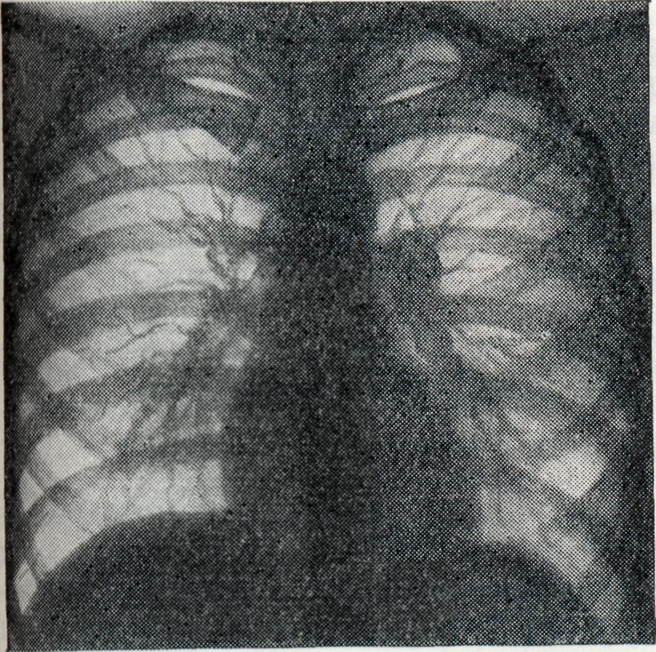

Серологические методы исследования: реакция агглютинации (Райта), реакция связывания комплемента (РСК), реакция пассивной гемагглютинации (РПГА), иммунофлюоресценции (Кунса), антитлобулиновая проба для выявления неполных антител (Кумбса) и другие. Реакция агглютинации — один из основных диагностических методов при Б. у людей и сельско-хозяйственных животных. Агглютинины, как правило, появляются в крови в ранние сроки после заражения, поэтому наибольшую диагностическую ценность реакция агглютинации представляет при острой форме Б. Помимо диагностической ценности, положительная реакция агглютинации может иметь и эпидемиологическое значение. РСК также является специфической для Б. Она появляется позже, чем реакция агглютинации, но держится дольше, что повышает её диагностическую ценность у больных хронический Б. Методика РПГА применительно к бруцеллезной инфекции разработана П. А. Вершиловой, М. И. Чернышевой с соавторами (1969). Гемагглютинирующие антитела можно обнаружить в 91—100% случаев у больных острым и подострым Б. При хронический Б. и резидуальных явлениях гемагглютинины обнаруживаются реже, однако в значительно большем проценте случаев, чем агглютинины. Зачастую гемагглютинины выявляются в тех случаях, когда все остальные реакции дают отрицательный или сомнительный результат. Специфичность и чувствительность реакции иммунофлюоресценции в динамике развития вакцинного и инфекционного процессов в условиях эксперимента, а также её диагностическая ценность у людей показана М. И. Чернышевой с соавторами (1967). В острой, подострой и хронический форме инфекции реакция иммунофлюоресценции выявляет антитела в сыворотке в несколько большем проценте случаев, чем реакция агглютинации. Высокая чувствительность пробы Кумбса при Б. доказана как у больных, так и у людей, находящихся в контакте с инфицированным материалом или животными, а также у лиц, проживающих в районах, неблагополучных по Б. крупного и мелкого рогатого скота. Аитиглобулиновая проба Кумбса рекомендуется в качестве диагностического метода при хронический и латентных формах Б. Пробу Кумбса можно применять для углублённого обследования людей и животных в целях ретроспективного выявления контакта с антигеном, а также изучения иммунологической структуры населения в очагах инфекции. Общепринятым методом ускоренной диагностики Б. у человека является пластинчатая реакция агглютинации Хаддлсона. В основе её лежит использование цельной сыворотки и антигена в концентрированном виде. Реакция специфична, становится положительной в раннем периоде заболевания и держится довольно долго. Преимущество пластинчатой реакции агглютинации по сравнению с пробирочной заключается в том, что постановка первой доступна в любой лаборатории и результат получается быстро. В процессе развития бруцеллезной инфекции у больных наблюдается повышение опсонической способности крови. В 1933 г. Хаддлсон, Джонсон и Хаманн (I. F. Huddleson, Н. W. Johnson, E. E. Hamann) предложили пробу для диагностики бруцеллеза — опсонофагоцитарную реакцию. Она основана на способности сегментированных нейтрофилов фагоцитировать бруцеллы благодаря наличию в крови человека специфических опсонинов, нарастающих в процессе бруцеллезной инфекции. Относительно высокий фагоцитоз наблюдается у лиц, не болевших, но соприкасавшихся с возбудителем заболевания, а также у вакцинированных живой вакциной. Реакция вполне специфична и чувствительна, однако она не отражает количества опсонинов в крови. Виктор (J. Victor) с соавторами (1952) предложили метод установления титров опсонинов в сыворотке крови. Все большее значение приобретает изучение состава сывороточных иммуноглобулинов в различные фазы бруцеллезной инфекции. В ранние сроки после заражения появляются антитела относящиеся к макроглобулинам (IgM). Микроглобулины (IgG) обычно выявляются в более поздние сроки. Определение иммуноглобулинов с помощью цистеиновой пробы приобретает диагностическое и прогностическое значение, а также способствует выбору рациональных методов лечения и более объективной оценке его эффективности. Проба Бюрне основана на способности организма, сенсибилизированного бруцеллезным аллергеном, специфически отвечать местной реакцией на внутрикожное введение небольших количеств аллергена (бруцеллина). Проба, как правило, становится положительной в 70—85% случаев к концу первого месяца заболевания, но бывают случаи и более раннего появления её (7—8-й день болезни). Реакция сохраняется очень долго, иногда годами. В отдельных случаях кожная проба может быть положительной и у клинически здоровых людей. В таких случаях она свидетельствует об аллергической перестройке организма под влиянием контакта с бруцеллезным антигеном, что нередко наблюдается у лиц, которые обслуживают больной Б. крупный рогатый скот. Кожная проба становится положительной и после вакцинации людей живой бруцеллезной вакциной. Серологические реакции и аллергическая кожная проба по своему диагностическому значению не равноценны, вследствие чего не могут заменить друг друга. Это обусловливает необходимость применения комплексного сероаллергического метода, являющегося наиболее надёжным способом диагностики Б. Смотри также Гемагглютинация, Иммунофлюоресценция, Кумбса реакция, Райта реакция, . Хаддисона реакция. Рентгенологическое исследование при Б. ранее ограничивалось главным образом изучением состояния опорно-двигательного аппарата, а следовательно, выявлением изменений в суставах, периартикулярных тканях, реже губчатых и трубчатых костях. Однако широкое применение рентгенологического исследования больных Б. показало, что и в фазах генерализации инфекции, и в латентном периоде встречаются также бруцеллезный внутригрудной лимфаденит (рисунок 5 и 6), бронхопневмонии и плевриты бруцеллезного происхождения. Лимфаденит при Б. проявляется рентгенологически в виде гиперплазии лимф, узлов корней лёгких, нередко с прикорневой инфильтрацией тяжистого или диффузного характера. Наблюдается как двустороннее, так и одностороннее поражение. В клинико-рентгенологическом аспекте следует иметь в виду быстрое возникновение, но очень медленное обратное развитие подобных изменений, что, впрочем, относится ко всем изменениям в лёгких при Б. В отличие от таких заболеваний, как саркоидоз, увеличение лимф. узлов при Б. не даёт картины резких полициклических бугристостей, прикорневая инфильтрация в начале процесса носит диффузный характер, свойственный скорее прикорневой инфильтрации при туберкулёзе, чем при болезни Бека. Признаки бронхостеноза при этом отсутствуют. Дифференциальная диагностика с лимфогранулематозом и ретикулосаркоматозом на основании одних лишь рентгенологических данных затруднительна и должна базироваться на картине крови, реакциях Райта, Хаддлсона и Бюрне.

Бронхопневмонии бруцеллезной этиологии также чаще всего обусловливают инфильтраты, связанные с корнем лёгкого, гл. обр. с хвостовой его частью. По рентгенологическим признакам их трудно отличить от бронхопневмоний, вызванных банальной флорой, в связи с чем необходимо учитывать общую картину заболевания, в частности наличие характерных для Б. периферических полиаденитов, фиброзитов, артритов, периартритов и т. д. Этими же соображениями следует руководствоваться при дифференциальной диагностике бруцеллезных плевритов.

Острые и хронический гематогенные диссеминации в лёгочной ткани также описаны при Б., хотя встречаются значительно реже, чем лимфадениты и бронхопневмонии. Гематогенные очаги Б. в лёгких мало отличаются от метастазов рака и гематогенного туберкулёза. Против туберкулёза говорит одновременное увеличение лимф, узлов корней лёгких, однако оно не обязательно. Положительные специфические реакции на Б. и отрицательные данные анализов мокроты и кожных проб на туберкулёз в сочетании с клиническим течением являются при гематогенно-диссеминированных формах Б. лёгких основными в установлении диагноза. То же следует учитывать в дифференциальной диагностике с метастазами рака и других злокачественных опухолей. Артралгии, часто сопровождающие стадию генерализации Б., как правило, рентгенологически бессимптомны, что, впрочем, также имеет важное значение в дифференциальной диагностике с полиартритами иного происхождения, в частности с ревматоидным полиартритом, при котором, как правило, относительно рано наблюдается остеопороз. Хорошо выявляемые клинически типичные для Б. периартриты, фиброзиты и поражения слизистых периартикулярных сумок в остром периоде Б. рентгенологически бессимптомны, но становятся рентгенопозитивными в фазе обызвесвления. Наиболее часты при Б. — подострые и хронический синовиты. Их преимущественная локализация — коленные, локтевые, голеностопные, реже лучезапястные и тазобедренные суставы. При этом виде поражений рентгенограммы обычно не дают указаний на деструктивные изменения, а пункция сустава — на присутствие бруцелл. Бурситы рентгенологически дают лишь картину умеренного локального остеопороза и увеличения объёма мягких тканей. В таких суставах, как коленные, выявляется понижение прозрачности хорошо видимых в норме заворотов сумки. Т. о., бруцеллезный бурсит на основании одной лишь рентгенологической картины не отличим от ревматического поражения и начальной фазы ревматоидного полиартрита. В отличие от описанных выше синовитов, истинные остеоартриты при Б. наблюдаются значительно реже и являются результатом формирования локального очага в костно-суставном аппарате, чаще всего в под-острой и хронически-рецидивной фазе заболевания.